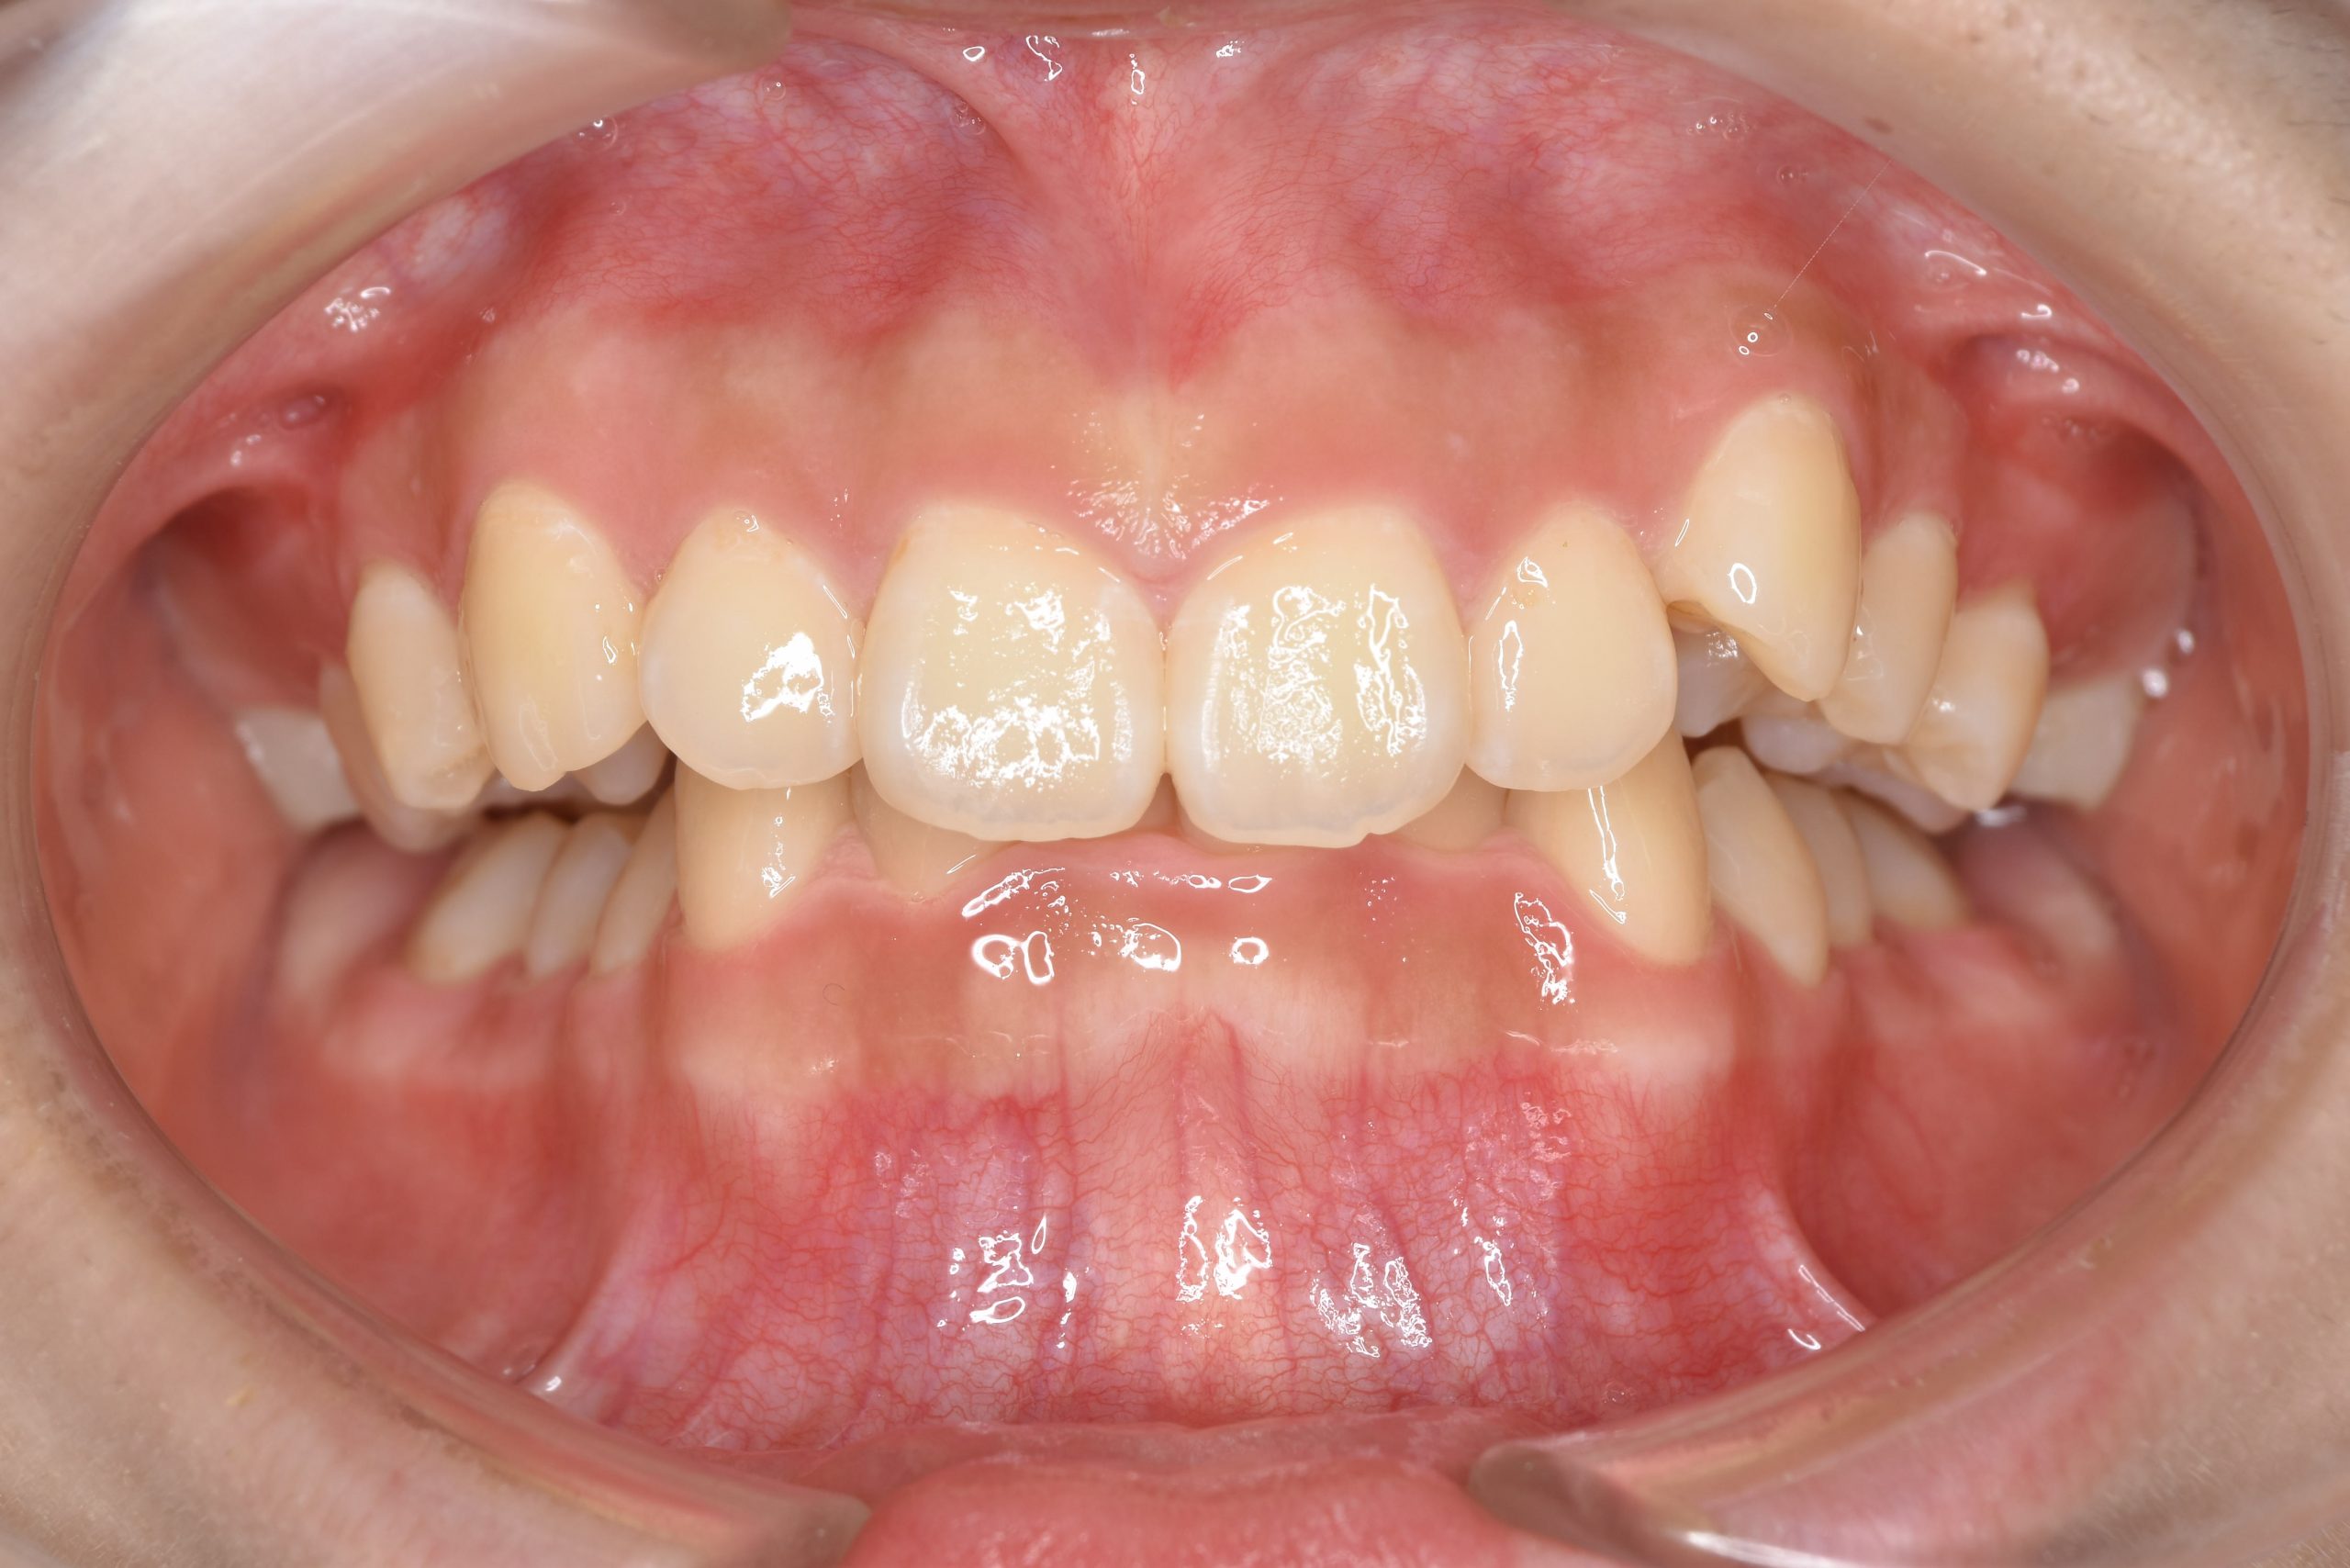

ビフォー

主訴 下の前歯が見えない|歯がガタガタ

施術内容 MSEと下顎リンガルアーチを用いて上下顎骨を拡大した。

その後マルチブラケット装置を用いて非抜歯で歯牙を配列し、良好な咬合を獲得した。